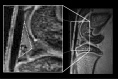

The purpose of present study was to longitudinally investigate the alterations in infrapatellar fat pad (IPFP) vascularity in 5/6 nephrectomized rats by using dynamic contrast enhanced (DCE) MRI and IPFP degeneration by using MRI T2* relaxation time. Twelve male Sprague-Dawley rats were assigned to a control group and a 5/6 nephrectomy CKD group. The right knees of all rats were longitudinally scanned by 4.7 T MRI, and serial changes in the IPFP were assessed at 0, 8, 16, 30, and 44 weeks by DCE-MRI (parameters A, kel and kep) and MRI T2* mapping. After MRI measurements, knee specimens were obtained and evaluated histologically. The CKD group had IPFPs with lower blood volume A and lower permeability kep values from 16 weeks (p < 0.05), lower venous washout kel value from 30 weeks (p < 0.001), and significantly higher T2* values reflecting adipocyte degeneration beginning at 16 weeks (p < 0.05). The histopathological results confirmed the MRI findings. Hypoperfusion and adipocytes degeneration related to CKD were demonstrated in a rodent 5/6 nephrectomy model. DCE parameters and MRI T2* can serve as imaging biomarkers of fat pad degeneration during CKD progression.